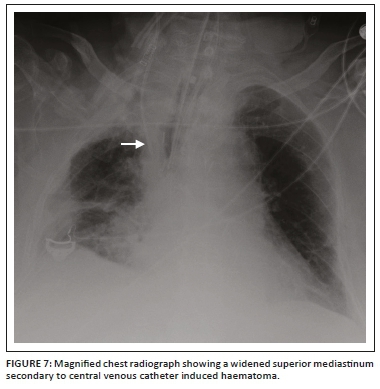

A central venous catheter (CVC), also known as a central venous pressure (CVP) catheter or a central catheter or line, is a catheter (Figure 5a) that provides access for administering drugs or fluids, monitoring central venous or pulmonary artery pressure, monitoring central venous blood oxygen saturation, transvenous cardiac pacing, access for extracorporeal blood products and interventions. These catheters are usually inserted via the subclavian or internal jugular vein and less frequently via the femoral vein. A peripherally inserted central catheter (PICC) is a CVC of smaller calibre (Figure 5b) that is usually inserted via the antecubital vein and remains in place for months.2,11,12 Tunnelled CVCs (Figure 5c) are cuffed catheters that provide long-term intravenous access for a variety of purposes, which include parenteral nutrition, chemotherapy and haemodialysis. The commonest application for this CVC is for haemodialysis in patients with renal failure.13

Most clinicians prefer the CVC tip to be positioned at or just above the cavoatrial junction. As the cavoatrial junction may be difficult to identify on a CXR, the most commonly used and reproducible landmark is two vertebral body levels below the carina. An alternative landmark would be the reflection of the SVC contour with the right heart border and the point where the bronchus intermedius intersects the right heartborder.14 A lower placement is preferred for cannulations introduced from the left side. The various types of CVCs, potential contraindications and complications are shown in Table 112 and Figures 6 and 7.